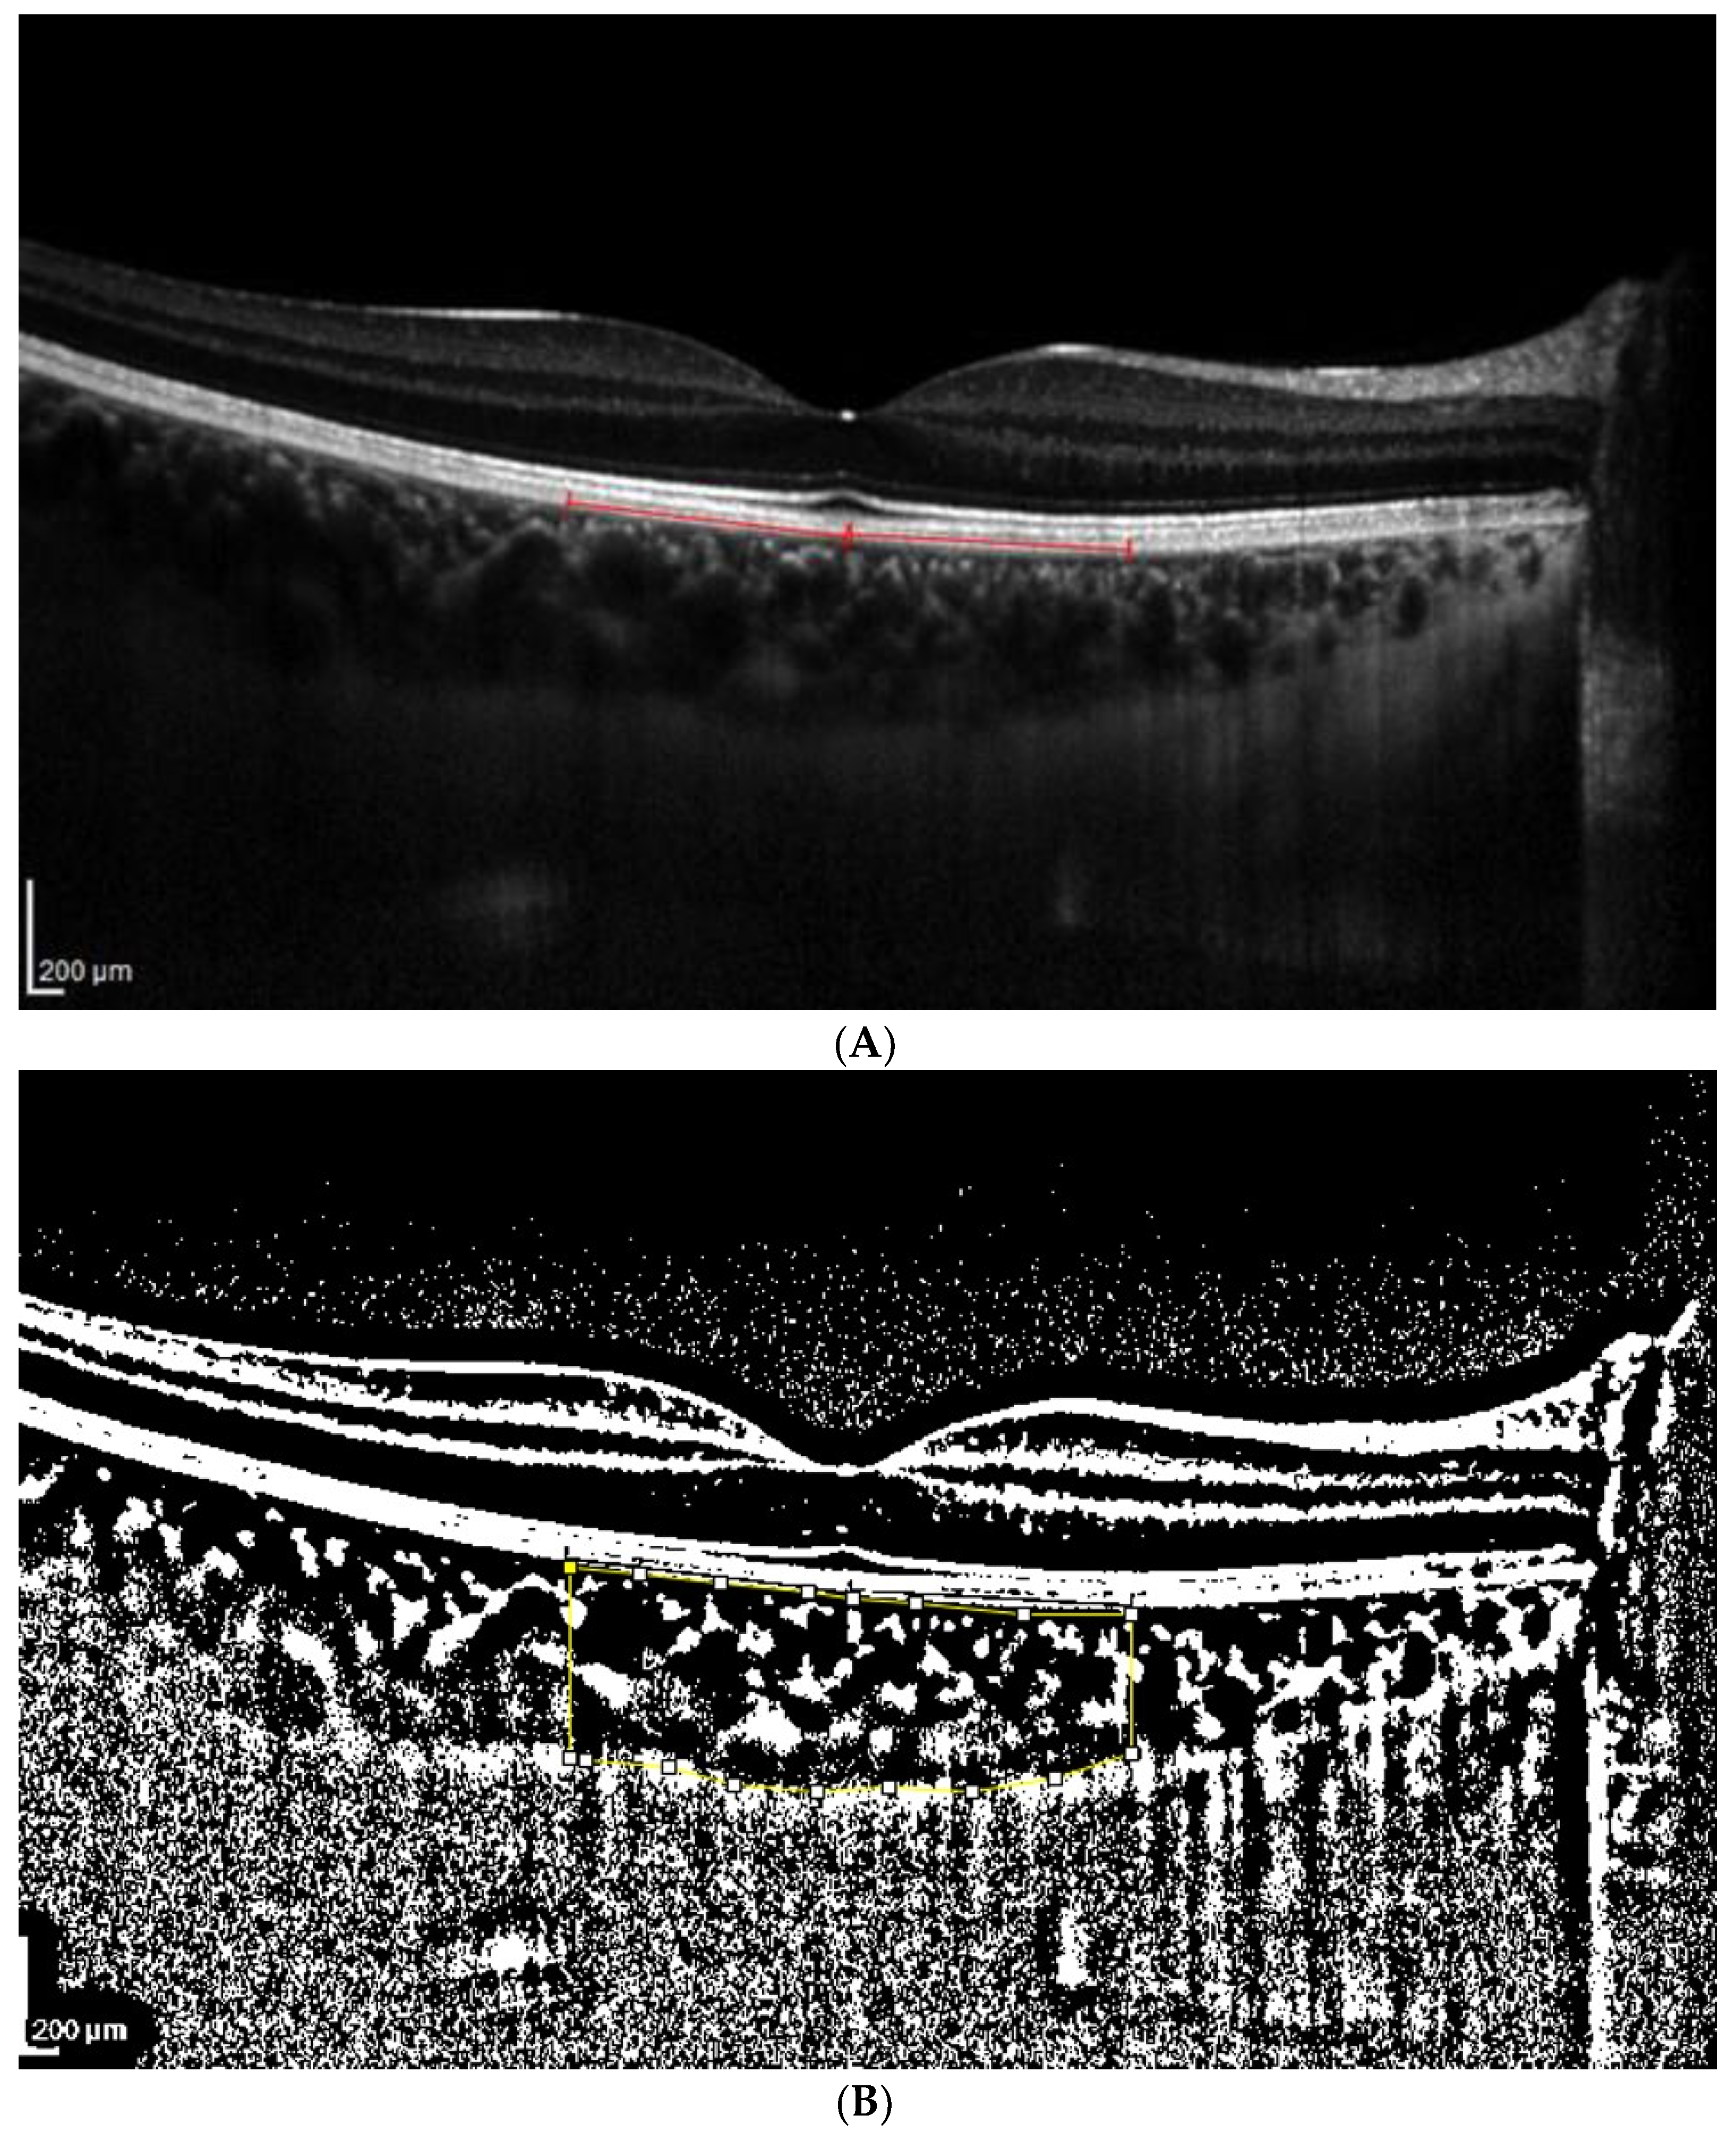

2.3. OCT Analysis

- A classic manual tracking method, manually drawing the lines to limit the choroidal area for each high and low brightness level [2].

- An alternative method, with a fixed area selection independent of the brightness level.